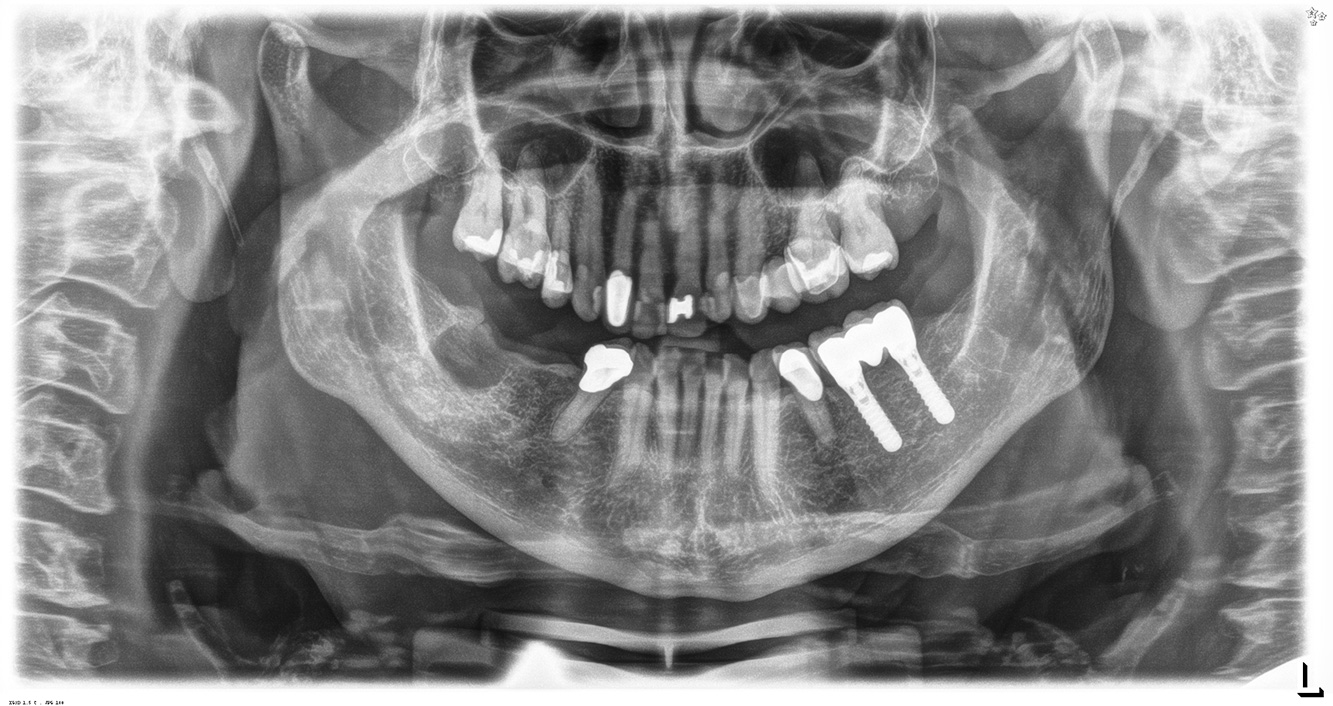

In the medical history, the 55-year-old patient states that he has no systemic disease and is not taking any medication. The patient’s lifestyle is similarly unremarkable. The patient has a few tooth restorations and two implants (2nd and 4th quadrants). On the basis of current findings, gingivitis is identified in an otherwise stable periodontal condition on the reduced periodontium (stage III, grade A). more

The healthy patient with pre-existing periodontal disease & peri-implantitis

Paciente sana con enfermedad periodontal previa

La paciente de 68 años no tiene enfermedades previas relevantes de la salud general ni toma medicación; sus hábitos alimentarios tampoco suponen un riesgo especial. La paciente tiene dos implantes (tercer cuadrante, desde hace cinco años) y una enfermedad previa periodontal (periodontitis en etapa IV, grado B) con pérdida dental. Actualmente las condiciones periodontales son estables, pero la periodontitis aumenta de manera determinante las complicaciones biológicas cuando se realizan implantes y puede ocasionar la pérdida de un implante (21). Para la sesión de profilaxis se hacen cuatro recomendaciones. más información